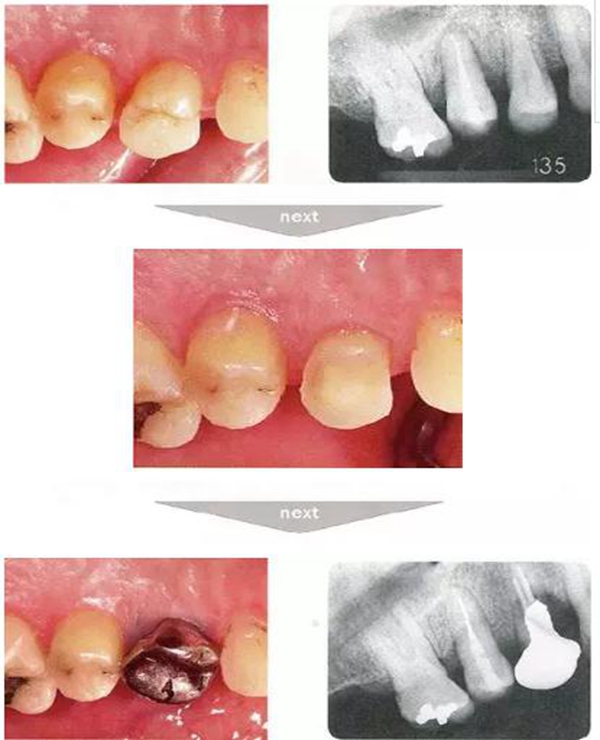

●與外傷相關(guān)的附著喪失①

右下4牙冠牙根破折案例。照片是破折前4個(gè)月拍攝的。牙周袋深度為3mm以下,牙周組織為正常狀態(tài)(右下5是以前由智齒矮小齒移植而來(lái))。破折后,舌側(cè)咬頭破折至傾斜的牙根處,破折片與牙齦相連。

去除破折片進(jìn)行了修復(fù)治療。3年后,上頜腭側(cè)有6mm、近中有4mm的牙周袋。X片可觀察到嚴(yán)重的骨吸收現(xiàn)象??赏茢喑鍪瞧普垡鸬母街鴨适?。

●外傷引起的附著喪失②

右上2修復(fù)物脫落而來(lái)院的患者(上圖是修復(fù)物臨時(shí)裝戴的照片)。頰側(cè)僅有一點(diǎn)有6mm的牙周袋。5個(gè)月前不存在此牙周袋。診斷為無(wú)法保存而進(jìn)行了拔牙。拔牙后,肉眼可清晰觀察到破折線。根據(jù)診查推斷為該深度牙周袋是由于牙根破折導(dǎo)致附著喪失,細(xì)菌沿著破折線進(jìn)入后破壞了牙周膜造成的。